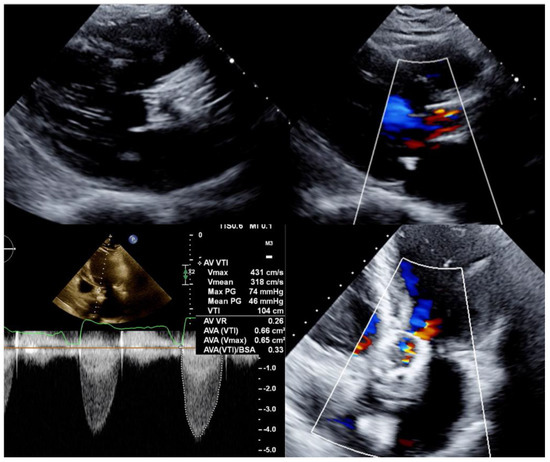

6.3. Procedure